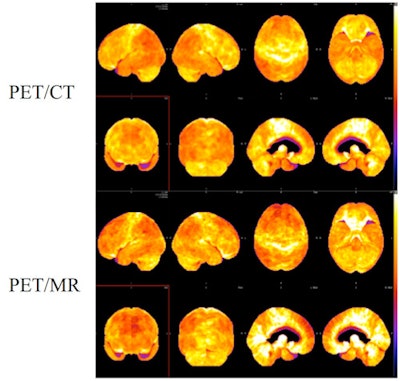

CHICAGO - Simultaneous PET/MRI can produce diagnostic-quality brain scans and interpretation results that compare favorably with PET/CT in patients with clinically suspected dementia, according to a study presented on Thursday at RSNA 2013.

Preliminary findings showed good concordance of diagnosis and severity of findings between PET/MRI and PET/CT when evaluated by two experienced nuclear medicine physicians, the researchers found.

In the study, 19 patients with clinically suspected dementia underwent a 15-minute PET/CT brain scan (Biograph mCT, Siemens Healthcare) 45 minutes after injection of 10 mCi of FDG. Simultaneous PET/MRI (Biograph mMR, Siemens) followed approximately 90 minutes after FDG injection.

When compared with PET/CT, PET/MRI interpretations yielded 84% (16/19) intrareader agreement in diagnosis. Also, 95% (18/19) of severity scores varied by one point or less between the two readers.

The second reader achieved 84% intrareader concordance of dementia pattern diagnosis, with 89% (17/19) of severity scores varying by one point or less.